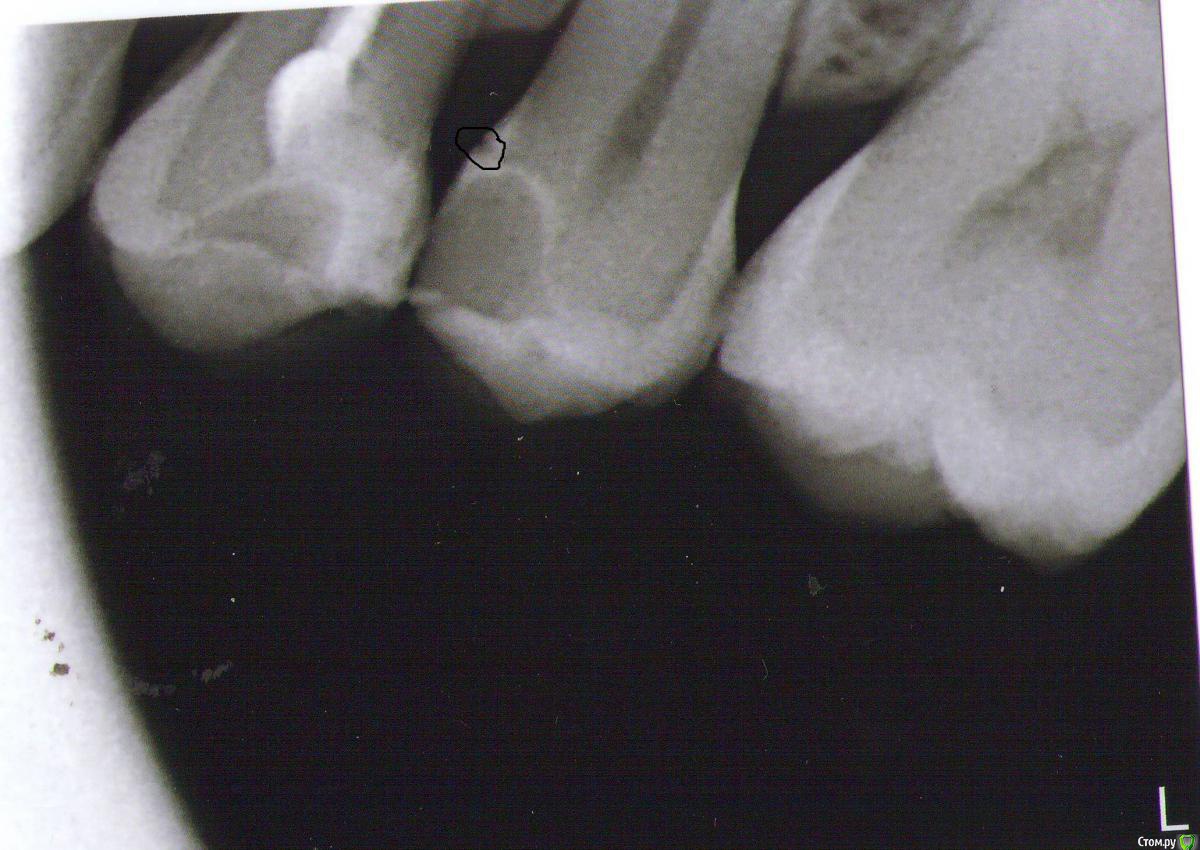

Darya87 Опубликовано 17 января, 2015 Автор Поделиться Опубликовано 17 января, 2015 (изменено) Сrazyduck, спасибо. И еще скажите, пожалуйста, бывает там между 4 и 5 зубом иногда застревает зубная нить, не может ли участок ниже пломбы на 5 зубе давать такой эффект?на снимке это место обведено черным Изменено 17 января, 2015 пользователем Darya87 Ссылка на комментарий